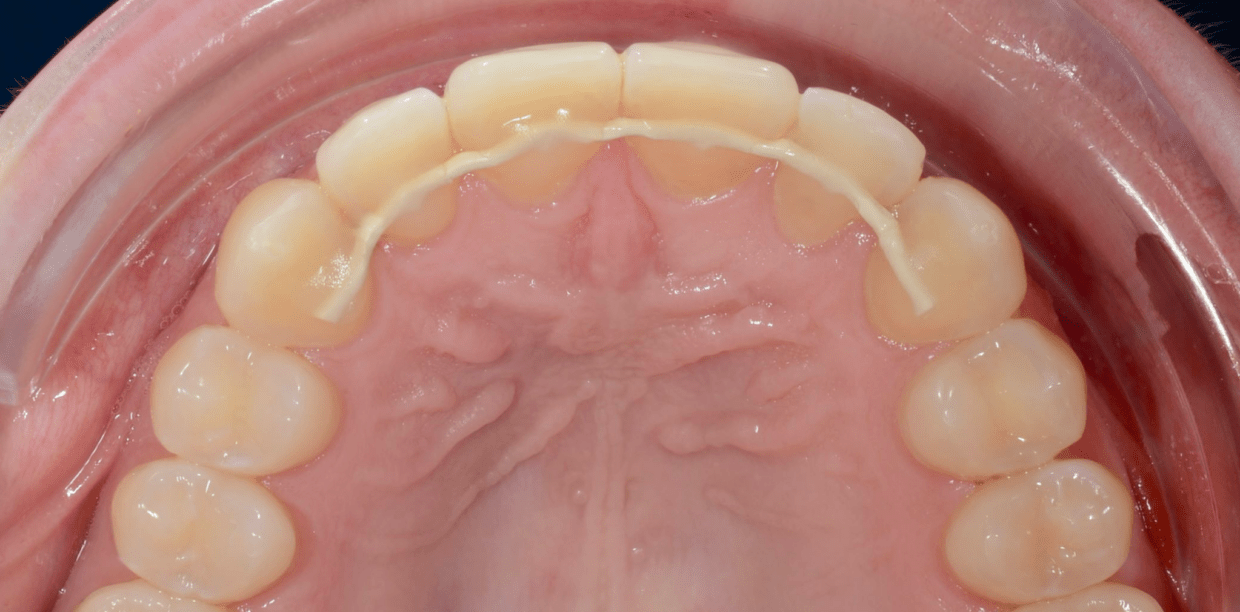

Cas cliniques

Simple - White

Simple - White

Simple - White

Simple - White

Simple - White

Simple - White

Simple - White

Simple - White

Simple - White

Simple - White

Simple - White

Simple - White

Simple - White

Simple - White

Simple - White

Simple - White